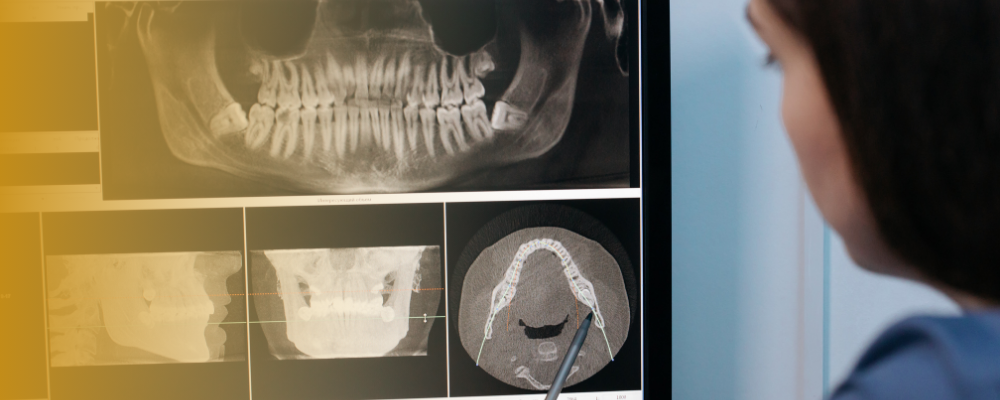

Mi az a panoráma röntgen és mikor szükséges?

A panoráma röntgen segítségével feltárásra kerül, hogy a fogászati megbetegedés okozhat-e más szervi elváltozást. Nagyon gyakori, hogy az állcsontokban, szájüregben lappangó gyulladásos megbetegedések más szervekben is panaszokat okoznak.